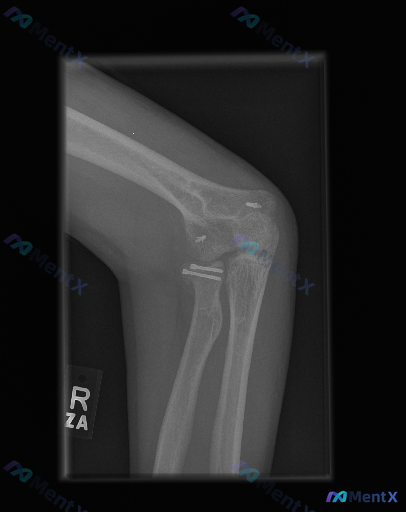

这个肘部侧位片有内固定,但固定位置有点奇怪,大家觉得术前可能是什么情况?

整理到一份肘部侧位X光的影像资料,先不说背景,大家看看这张片的异常,以及为什么会用这样的固定方式?

影像核心所见(先整理客观部分):

- 体位:肘关节侧位,成人骨骺已闭合

- 内固定:桡骨头/颈区2枚平行螺钉;肱骨远端关节周围2枚植入物

- 骨性结构:桡骨头颈见陈旧骨折/术后愈合痕迹;无明显新鲜骨折/脱位

- 其他:无明显脂肪垫征,无明显游离体,有金属伪影

第一眼很容易归为「术后改变」,但仔细想:单纯外伤性桡骨头骨折,通常很少同时在肱骨远端也打钉子固定。

大家觉得这种「跨关节、多点位」的固定模式,术前更可能是什么情况?下一步如果要排查,最想先补什么信息?